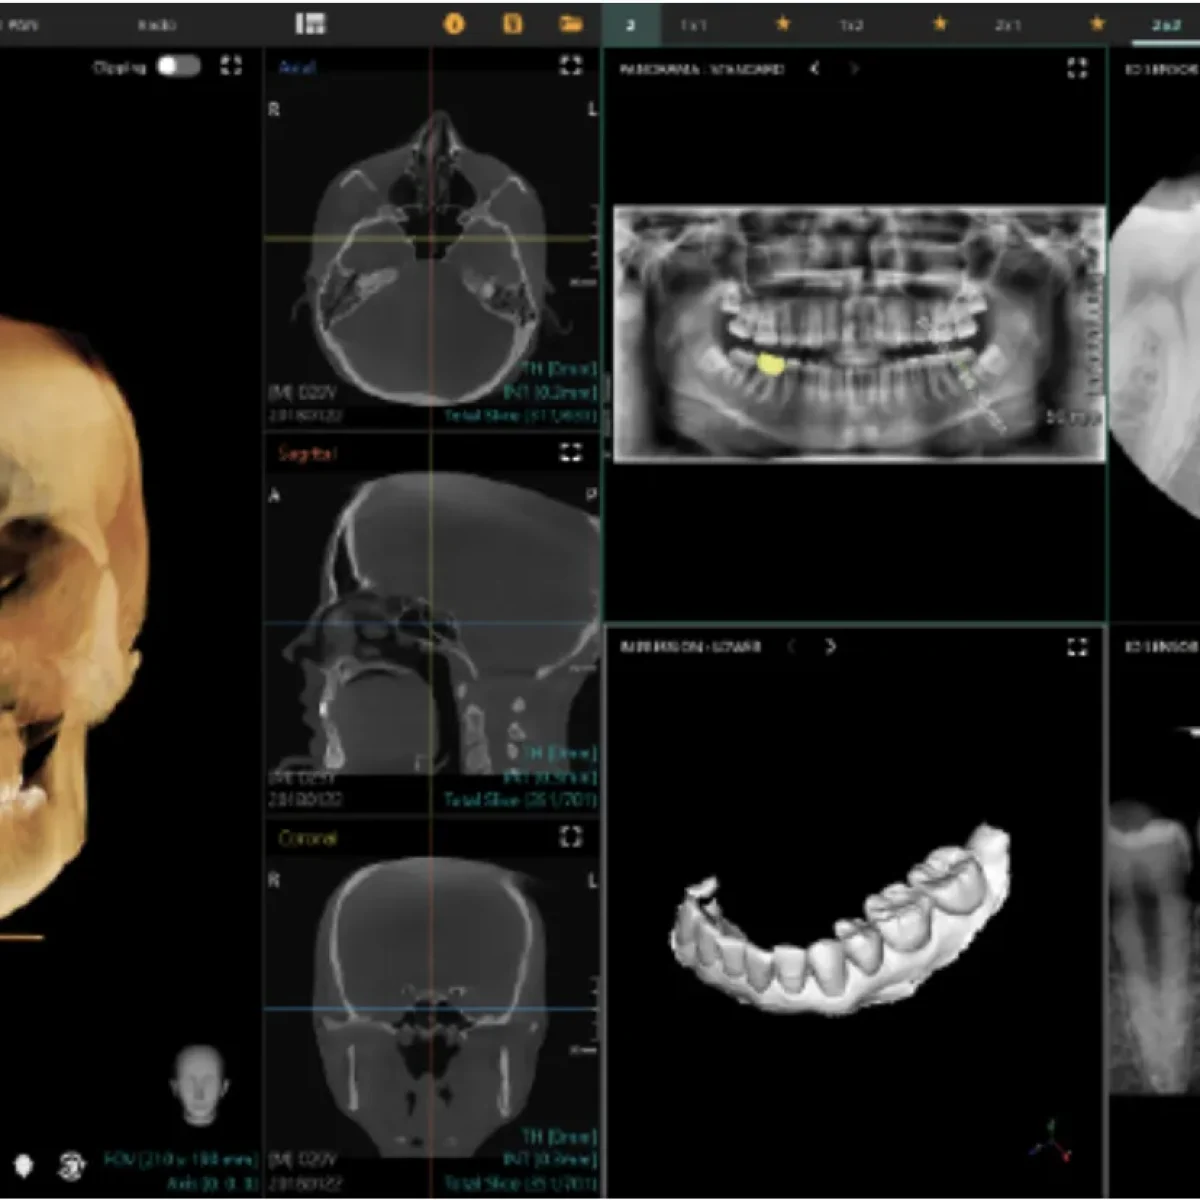

3D CBCT Imaging

Our Cone Beam CT (CBCT) scanner produces a detailed 3D view of your teeth, bone, nerves, and soft tissues—allowing for exact diagnosis and surgical planning.

This technology enables:

• Pinpoint accuracy for implant placement

• Safer surgical navigation around nerves and sinuses

• Improved diagnosis of infections and fractures

• Better communication with referring doctors

With this level of clarity, no guesswork is ever involved—only precision.